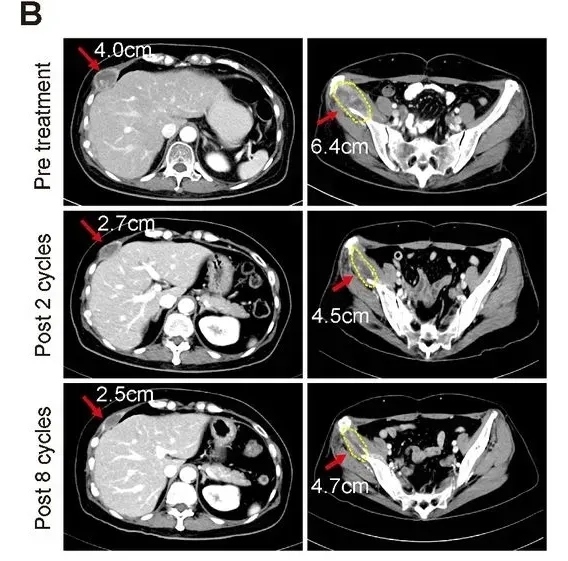

更值得关注的是其中一位55岁特殊患者的治疗突破——她同时患有转移性激素受体阳性+HER2阳性乳腺癌,既往已历经抗HER2治疗、激素疗法及多种化疗,抗癌之路多次陷入困境。但在接受连续2个周期联合治疗后,患者成功达到部分缓解(PR),且这一良好状态持续至第8周期(详见下图)。同时,她的肿瘤标志物CA-153水平也出现显著下降:治疗前为146.8,治疗第5周期降至75.4,治疗结束时仍稳定在76.6,从分子层面印证了联合疗法的切实疗效!

▲图源“AACR”,版权归原作者所有,如无意中侵犯了知识产权,请联系我们删除